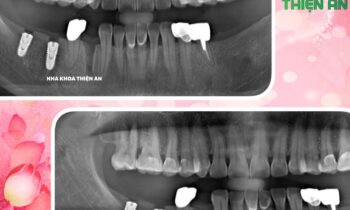

MÀNG PRF KẾT HỢP IMPLANT TẠI NHA KHOA THIỆN AN

Tiếp tục cấy ghép thêm 1 trụ implant cho chị D sau khi chị trải nghiệm cắm 2 trụ implant tại nha khoa Thiện An BMT – Đăk Lăk nhẹ nhàng, êm ái, với công nghệ Màng PRF được chiết lọc từ chính máu tự thân của chính bệnh nhân để tạo ra các tế…